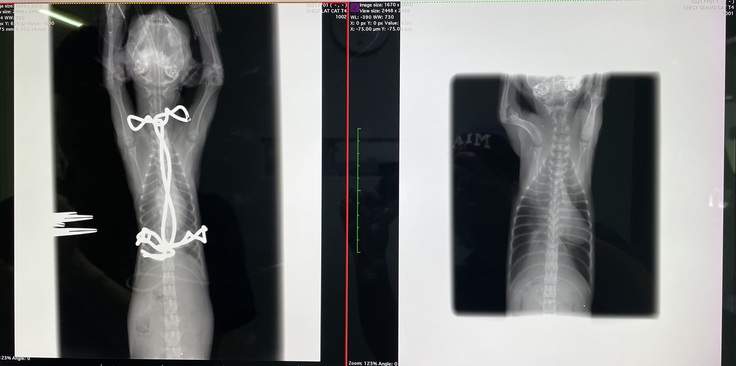

漏斗胸の胸骨矯正手術が無事に終わりました。

思ってたより骨が変形していたそうで、肋骨の軟骨もすごい形をしていたそうです。歪んでいた心臓も術後はほぼ正常な位置に戻りました。

すごく骨が変形していた為、完全には綺麗な形にはならなかったみたいです。成長していくにつれて、少しずつコルセット(ギプス)を調整していき、様子を見ていく、とのことでした。

※写真 (左)after (右)before